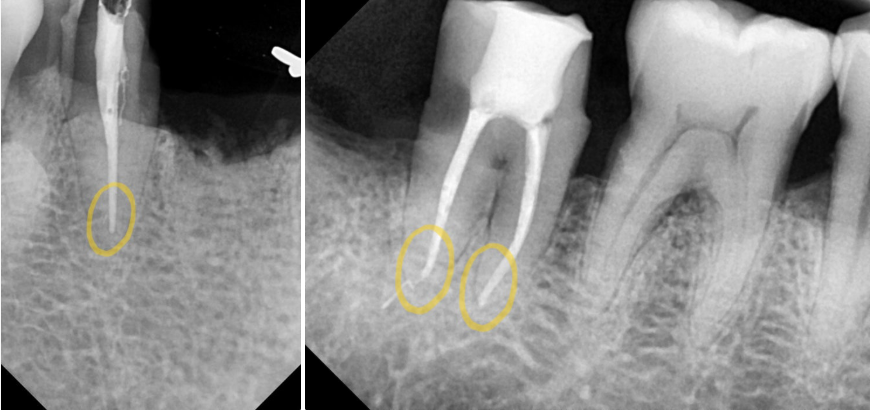

전치부 / 구치부

숨어있는 미세 근관까지 빼곡하게 채워주었습니다.

파노라마 사진을 보면 뿌리 끝까지 채워진 모습을 볼 수 있네요.

본격적으로 식립을 하기에 앞서,

골질과 골양, 주변 조직과의 관계를 확인했습니다.

이후 총 5곳에 implant fixture를 심은 다음

잇몸 형성에 도움을 줄 healing abutment까지 체결을 도왔습니다.

연결 이음새 부분이 매끄럽게 잘 이어지고 있는 모습이네요.

식립 후 CT